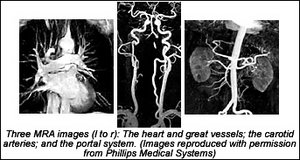

Conventional angiography remains the gold standard for evaluating the vascular system, but MRA is playing an increasingly important role: providing a safe, cost-effective, and accurate alternative for many angiographic procedures. In many centers, MRA has replaced some diagnostic angiography, and with the recent advances in MR hardware and software, MRA can provide high-quality diagnostic images of arteries and veins throughout the human body.

Today, MRA is usually used to describe an imaging technique in which blood flow appears bright. The first "bright-blood" technique to achieve widespread clinical use was "time-of-flight" MRA. Early time-of-flight protocols were limited by poor spatial resolution, flow artifacts, and long acquisition times. With the introduction of faster, more powerful gradient systems and improved pulse sequence design, these problems have diminished. Both 2-D and 3-D time-of-flight MRA are now used routinely for many MRA examinations, particularly of the carotid arteries and intracranial vessels.

The introduction of contrast-enhanced (CE) MRA has fueled the rapid growth of MR applications for evaluating extracranial vessels. The problems of signal loss from turbulent flow and in-plane flow saturation have been virtually eliminated with this technique. Three-dimensional CE-MRA techniques can now be performed within a single "breath-hold" on most current imaging systems. This is particularly important for abdominal applications, such as assessment of the renal arteries.